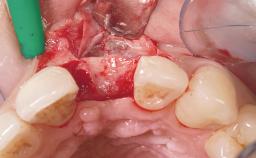

Late Flapless Placement of an Implant in a Maxillary Left Central Incisor Site

A 39-year-old male patient presented with a chief complaint of discomfort and gingival discoloration around his maxillary left central incisor. He was in good general health and was a non-smoker. His past dental history was significant because of the traumatic fracture of tooth 21 in a sporting accident at age 13. Initial dental treatment included endodontic therapy and a full-coverage restoration. The patient became symptomatic 5 years later, when structural failure of the tooth resulted in the dislodgment of the crown. Endodontic retreatment, apical surgery, and post-and-core restoration were performed.

Soft Tissue Grafting Simultaneous

Bone Volume Deficient horizontally, requiring prior grafting